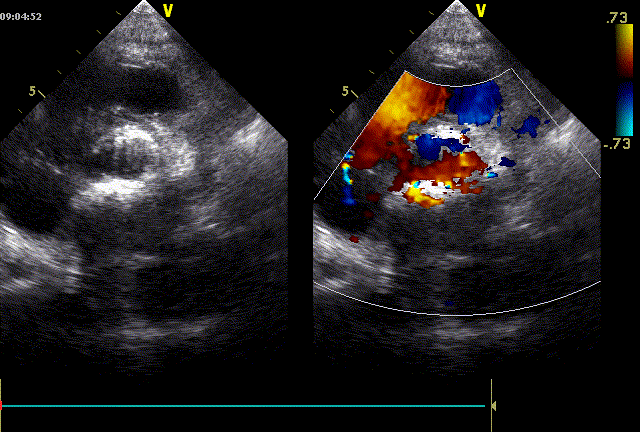

心脏超声示:主动脉瓣重度狭窄伴轻度关闭不全;二尖瓣中度狭窄伴轻度关闭不全;三尖瓣轻度反流;心包积液(少量)。